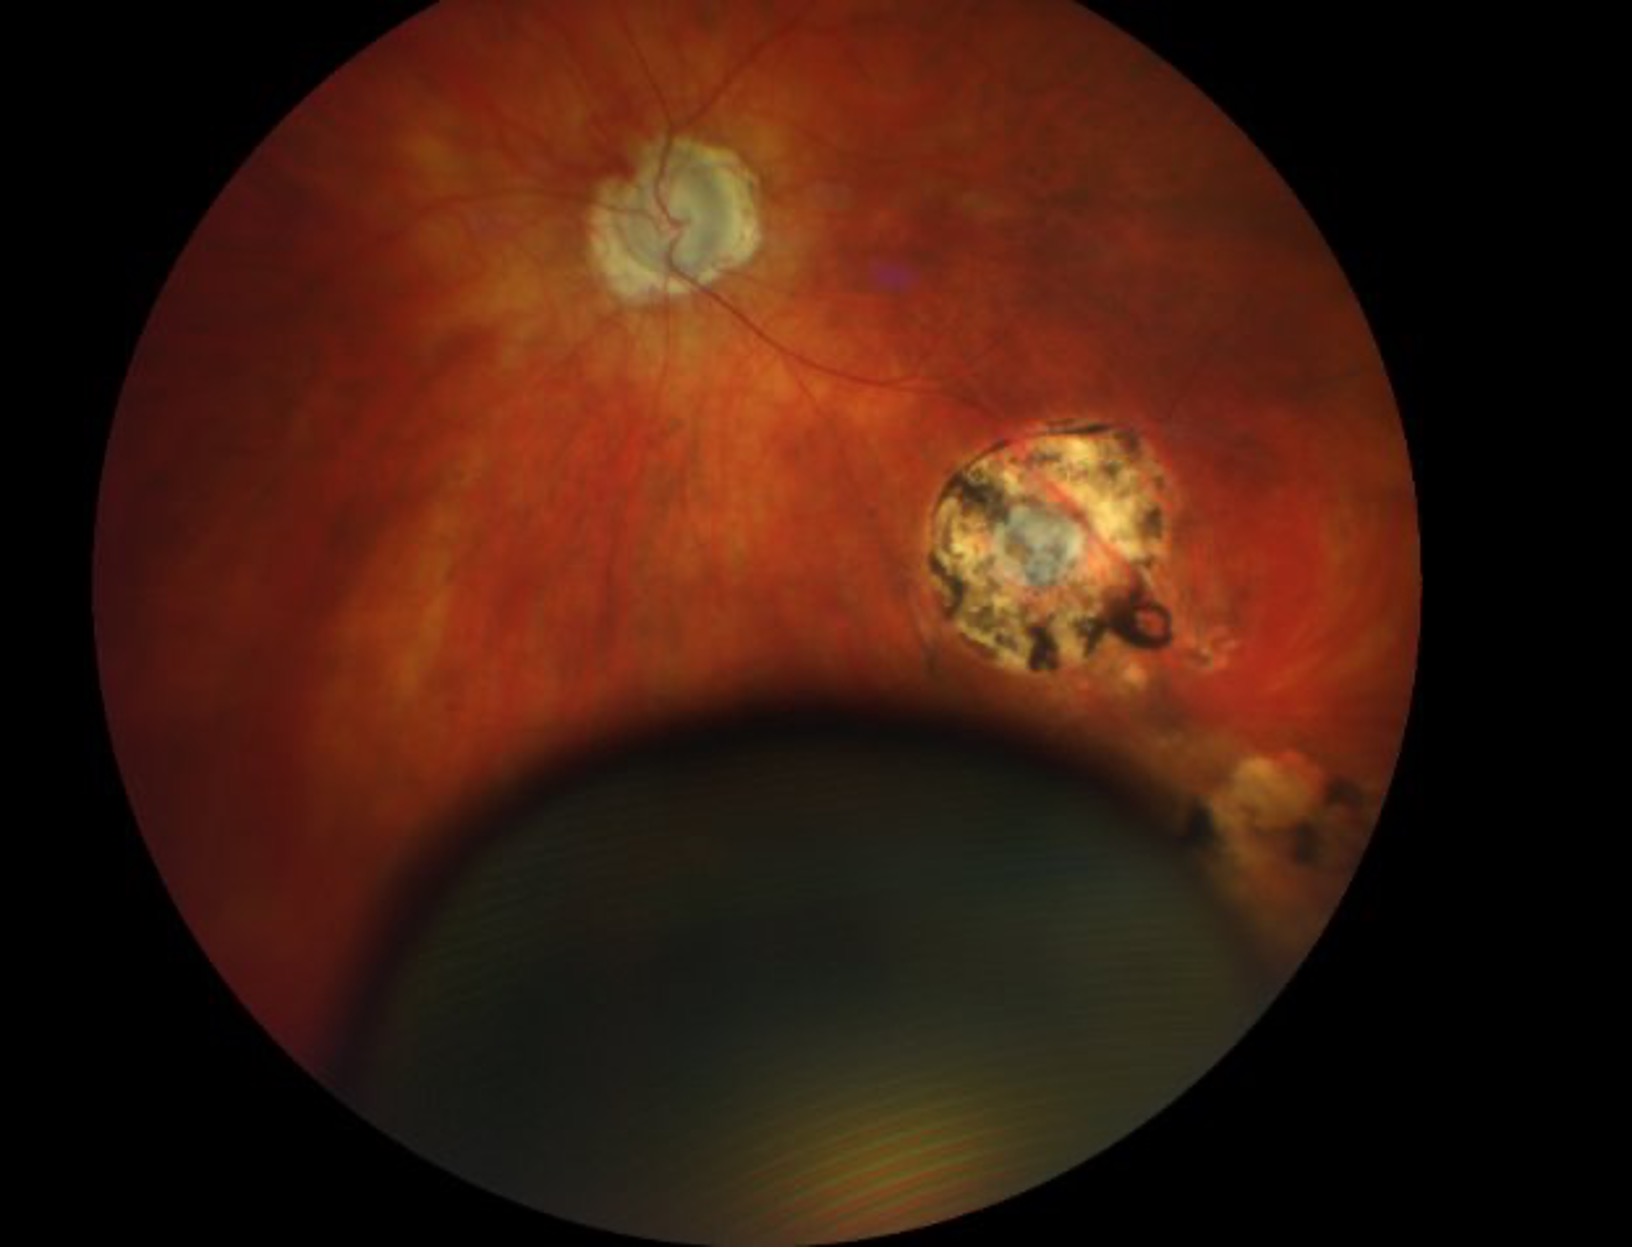

• This is a fundus photo of the left eye showing clear media, diffusely pallid disc, a chorioretinal scar along the inferotemporal arcades near the equator, and a large bulbous mass in the inferior quadrant.

Figure 1. This is a fundus photo of the left eye showing clear media, diffusely pallid disc, a chorioretinal scar along the inferotemporal arcades near the equator, and a large bulbous mass in the inferior quadrant.